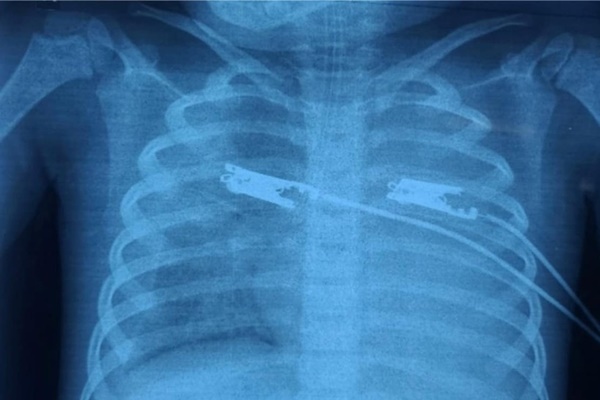

Bệnh nhi được giúp thở do tổn thương phổi, truyền máu, dùng kháng sinh. Ảnh: BVCC

Bệnh nhi được giúp thở do tổn thương phổi, truyền máu, dùng kháng sinh Vancomycin và Carbapenem do tình trạng viêm phổi nặng, nhiễm khuẩn huyết và suy đa cơ quan nặng. Sau 2 ngày, kháng sinh trên không đáp ứng, bé vẫn sốt cao kéo dài liên tục.